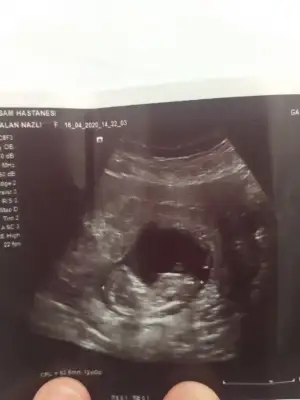

Merhabalar bana da tahminde bulunur musunuz rica etsem 11 haftalık teşekkürler şimdidenBuraya paylaşın mesaj yazdıgınızın hemen sol altta dosya ekleye tıklayın![]()

Şimdilik kız gibi sanki 12-13 haftasınıda paylaşın

Kime yazdınız alıntı yapın yada cevaplaya tıklayın kime yazacaksanız sorunun altında cvpla varKız gibi duruyorallah hayırlı saglıklı bi şekilde kucagınıza almayı nasip etsin